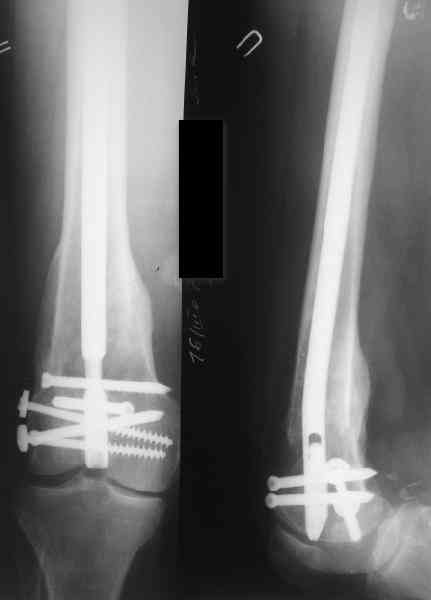

В приложении пример, как их использовали после остеотомии бедра по поводу сросшегося с вальгусом перелома, чтобы не дать гвоздю уйти во внутренний мыщелок.

В приложении пример, дистальный отломок пружинил кзади. Два винта потому, что первый оказался чуть кпереди и не упирался в гвоздь.